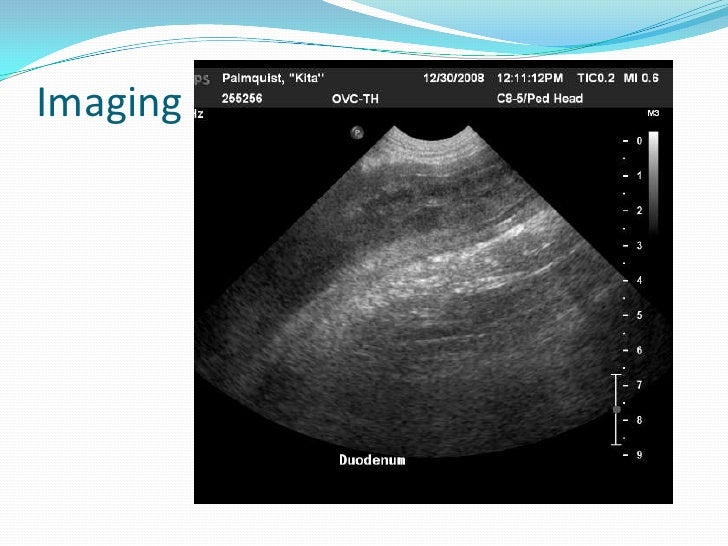

PPT - Clinical Grand Rounds PowerPoint Presentation, Free Download - ID

PPT - Clinical Grand Rounds PowerPoint Presentation, free download - ID www.slideserve.com

rounds bacteria killing antimicrobial

rounds preparations efficacy bacteria